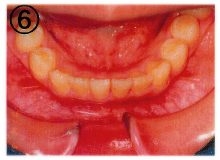

当医院では「床(しょう)矯正」という矯正治療を実践しております。

基本的には永久歯を抜かず、顎を拡げて歯を並べる治療の事です。

床矯正で使用する装置は簡単に取り外せるので、虫歯や歯周病を患いにくく、清潔な口腔環境が保てます。